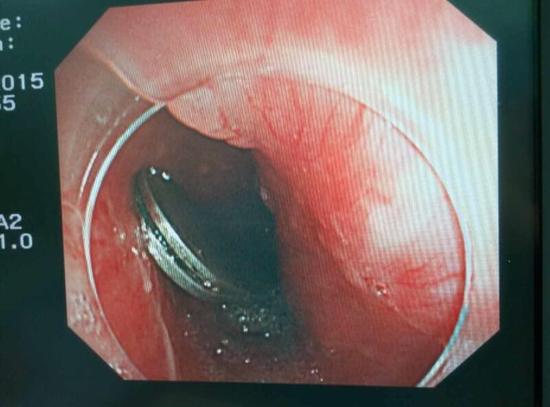

醫(yī)生從華先生胃里取出的鑷子和打火機(jī)

手術(shù)中,范醫(yī)生通過胃鏡準(zhǔn)確發(fā)現(xiàn)了胃里的鑷子。但讓他驚訝的是,在華先生胃底竟然還躺著三個(gè)被腐蝕了的打火機(jī),打火機(jī)的金屬部件都已經(jīng)不見了。

隨后,范醫(yī)生先用圈套器套取出了長(zhǎng)10厘米的鑷子,再一個(gè)一個(gè)地取出了打火機(jī)。整個(gè)取出過程小心謹(jǐn)慎而又一氣呵成,只用了不到10分鐘。